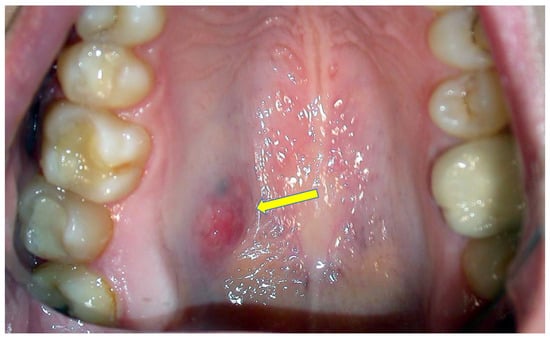

During the observational period, 128 MECs were identified, 82 involving the major and 46 the minor salivary glands; among these, 14 showed an exclusive intra-cystic tumoral component in the absence of infiltration of the adjacent tissues, as confirmed by the evaluation of additional cutting levels, the salient clinico-pathological features of which are reported in Table 1. Among such patients there were three males and 11 females, with a median age of 36.8 years; nine MECs involved the hard palate, two cases the soft palate, two the cheek mucosa and one case the retromolar trigone. In all instances, the neoplasms appeared as intra-oral nodules (Figure 1), sometimes with slight erosion/ulceration of the surface epithelium; and showed painless, slow growth and hard consistency, without evident infiltration of the adjacent soft and hard tissues, as confirmed by MR (conventional acronym for Magnetic Resonance) and CT scans. The tumor dimensions were relatively small, with a minimum clinical diameter of 0.5 cm up to a maximum of 1.8 cm. No loco-regional node involvement was detectable by clinical inspection or imaging techniques in any instance. All patients underwent conservative surgical excision with a rim of normal tissue. It should be emphasized that all the tumors of this cohort were localized in minor salivary glands and we were unable to identify “pure” intra-cystic (in situ) MEC in major glands.

Figure 1. Clinical presentation MEC of the hard palate as a rather well-demarcated nodule with slight erosion of the covering mucosa.